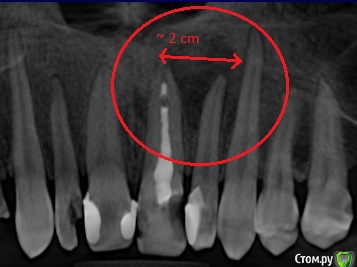

WhiteJaguar Опубликовано 30 сентября, 2017 Поделиться Опубликовано 30 сентября, 2017 (изменено) Здравствуйте, такая ситуация. Давно ещё в 90 + годах, лечил зуб. Удалили нерв, заполнили канал, поставили пломбу. Зуб передний резец слева. Спустя много лет, ~ 2010г. врач лечил другой зуб, но направил на рентген этого. Рентген я сделал, но к врачу больше не попал из-за обстоятельств. Так это дело и зависло. Потом в ~2015 на челюсти появился флюс над этим зубом. Я обратился к врачу, прописали метронидозол и найз, вскрывать не стали. Так как я пришел не в свою больницу и без записи. А раб. день заканчивался и врачи торопились домой. Начал пить метронидозол, всё как рукой сняло и флюс пропал и боль. Я думал что всё хорошо. Но в конце 2016 опять вскочил флюс на коренных зубах с той же стороны, сделали разрез, всё почистили, поставили дренаж коренной зуб удалили. Врач направила на КТ. КТ я сразу делать не стал. Совсем недавно, на прошлой неделе опять вскочил флюс на нёбе, в районе корней этого переднего зуба. Пошел делать КТ. По КТ врач сказал, что все из за некачественной пломбы и образовавшейся пустоты в канале или десне, не помню.. Это стало очагом воспаления. В результате чего образовалась киста диам. ~2см.Врач сказала, что киста рассосала кость, но кость можно восстановить если зуб не удалять, а перелечить - убрать очаг воспаления и пролечить зуб. А киста пропадёт если зарастёт костью. А удаление будет выглядеть не эстетично и потом дорогостоящее заполнение пустоты и установка импланта. У меня такие вопросы: 1. как будет выглядеть не эстетично если я зуб удалю и образуется полость из-за кисты ? Внешне ? То есть с виду на лице будет вмятина или внутри в полости рта ? 2. может ли киста играть роль каркаса для образования кости ? Читал, что кость восстановиться может, но ей нужен каркас. 3. Если я зуб пролечу, какова вероятность, что именно с этим зубом всё повторится ? Останется ли он таким же проблемным после лечения если всё удачно пролечится или он станет на ровне с остальными зубами ? 4. что всё таки делать, удалять или лечить и почему ? Сейчас у меня флюс так же остался, пью амоксиклав, прикладываю левомеколь. Болей нет но при надавливании в нёбе на это место чувствуется неприятное ощущение и шишечка от флюса осталась.Вот сижу думаю что дальше делать. Снимок прилагается Просьба ответить на все вопросы ! Благодарю. p.s. интересно пчму врач предложила сразу перелечивать зуб без прореза флюса. Ведь до того что бы удалить зуб сказали надо сначала почистить полость с флюсом, а потом удалять что б не было заражения. А тут сказали всё через канал уйдет.. Изменено 30 сентября, 2017 пользователем WhiteJaguar Ссылка на комментарий